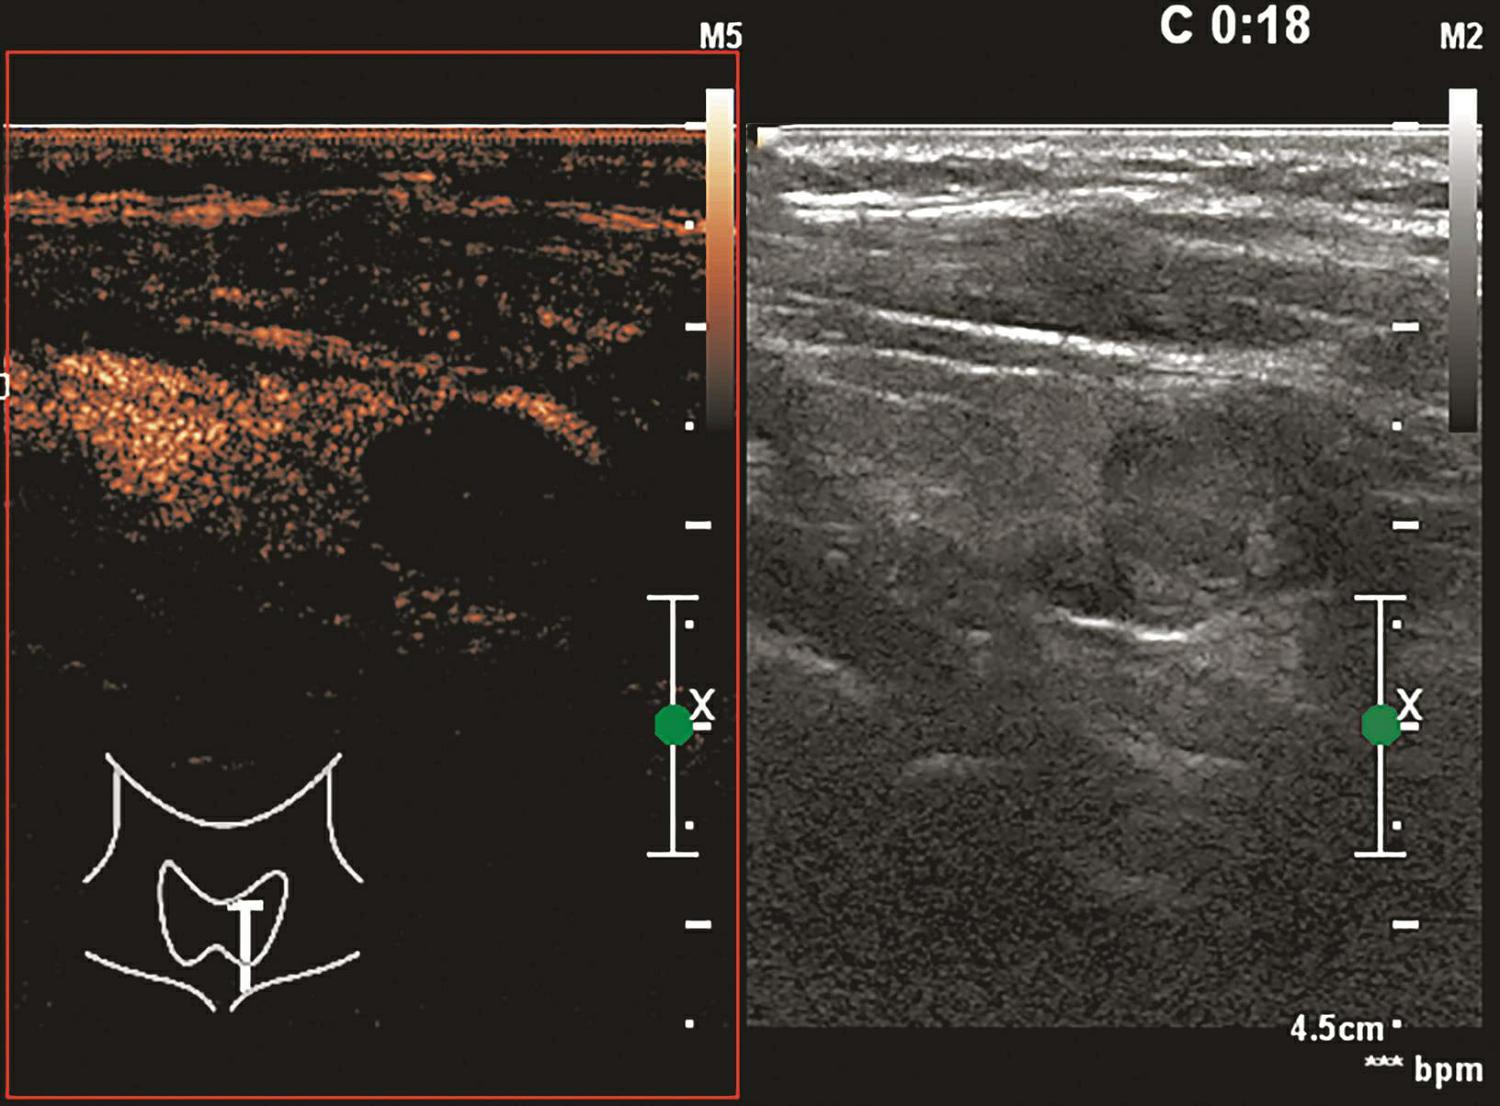

甲状腺囊肿常规超声表现为边界清晰、形态较规则的无回声结节,内可见点状强回声,后伴“彗星尾”征,CDFI内部无明显血流信号,见图1-3-1。

图1-3-1 甲状腺囊肿常规超声声像图

A.甲状腺左叶纵切面;B.CDFI血流图